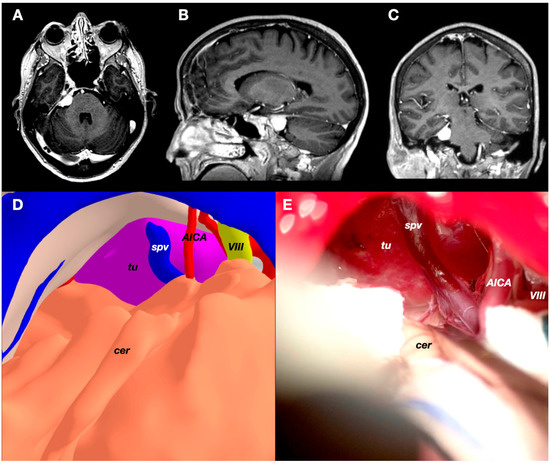

3.3. Case 3: Petrous Apex Meningioma